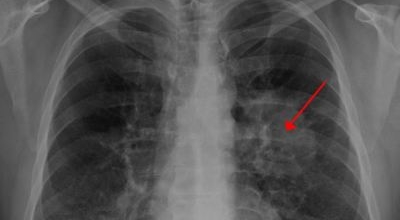

폐암 검사는 X-ray를 통해서 검사하는데 , 크기가 작거나 구석에 위치한 경우 확인이 어려운 경우도 있습니다. 그리고 조직 검사를 통해서 정확한 진단을 하게 되어요. 폐암이 발견되면 종양의 크기나 전이 여부 , 위치에 따라서 수술 여부를 결정하게 돼요.